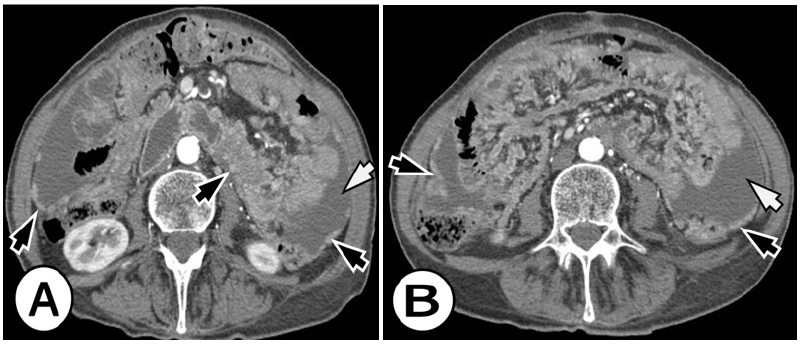

Figure 2A&B: Peritoneal carcinomatosis from signet ring cell gastric carcinoma in a 63-year-old woman. Axial arterial phase CT images in the level of the kidneys, revealed multifocal nodules in the peritoneal cavity, peritoneal enhancement and thickening (black arrows), and ascites (white arrows).